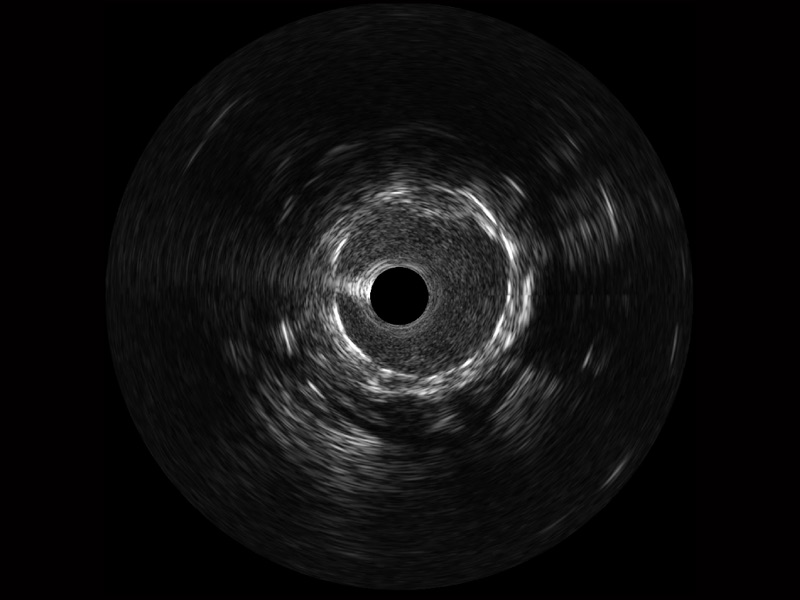

開立寬頻IVUS圖像

傳統(tǒng)IVUS圖像

對(duì)比傳統(tǒng)IVUS導(dǎo)管成像,開立寬頻IVUS圖像的近場(chǎng)支架梁顯影更細(xì)膩,遠(yuǎn)場(chǎng)中膜外血管仍清晰可辨,兼顧遠(yuǎn)中近,兼顧分辨力與穿透深度